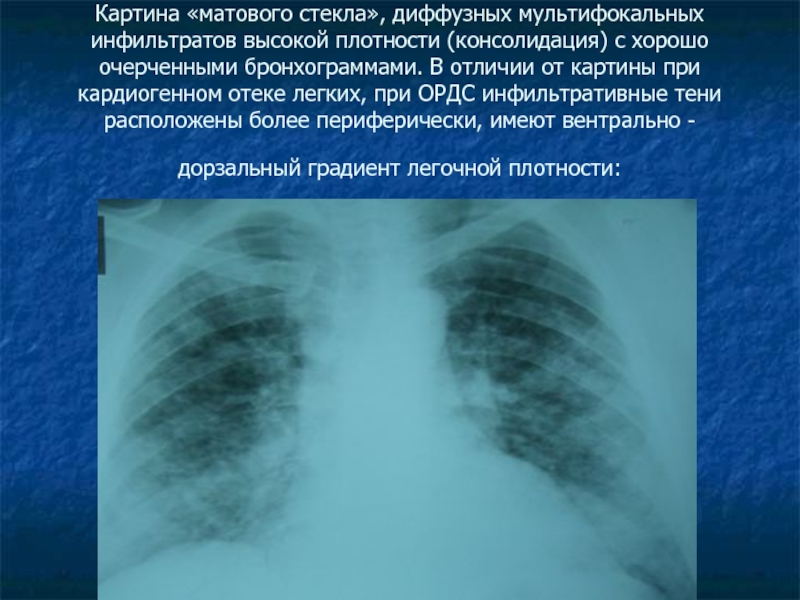

Фотографии, демонстрирующие обнаруженное усиление легочного рисунка

Раздел: Фотодневник открытий